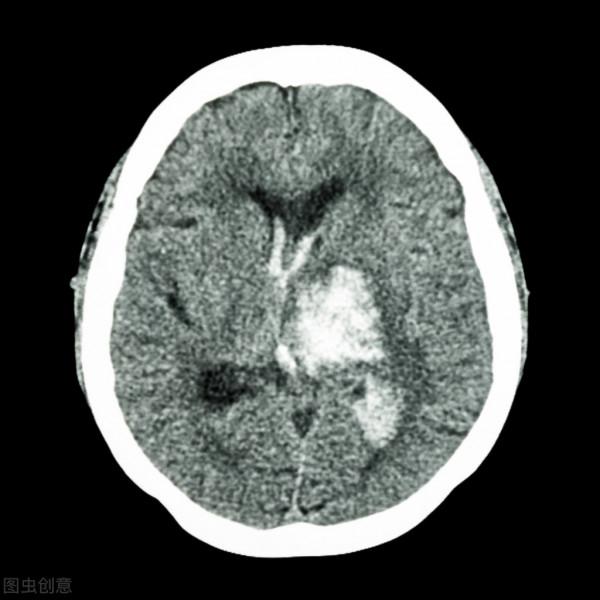

腦卒中包括很多種,比如腦出血、腦血栓形成和腦栓塞,其實這些都屬於腦卒中。

曾有學者統計過,在需要住院的急性缺血性腦卒中患者當中,一個月之後的死亡率可以達到2.3%~3.2%,而三個月之後死亡率會更多達到9%~9.6%。

而腦出血的發病更為兇險,有研究表明三個月內腦出血的死亡率甚至可以達到20%~30%。